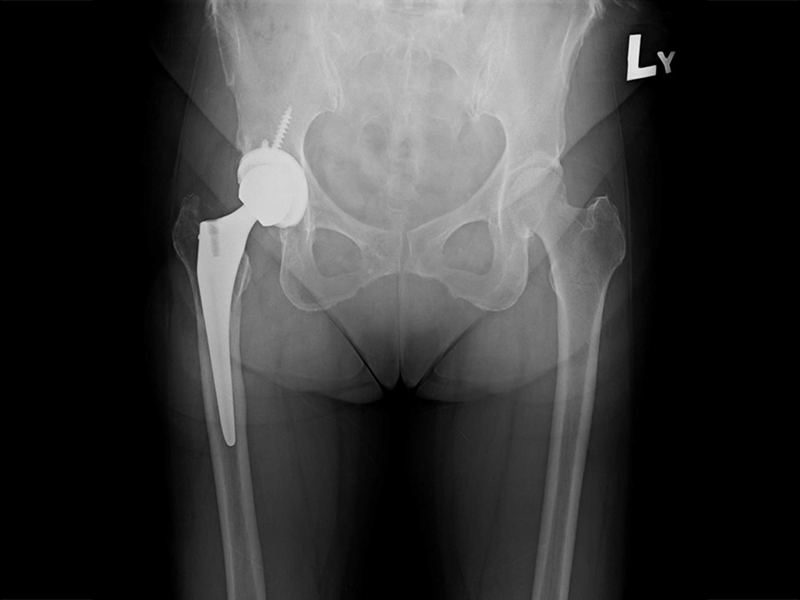

髖關節手術